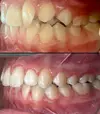

Crooked Teeth

Porcelain applications

Laminate veneer